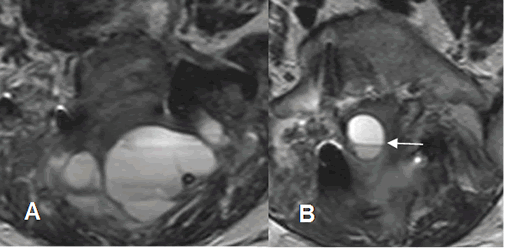

Fig 129C. Compresión postQx.

A y B: RM axial en T2. Igual paciente anterior. Colección de tejidos blandos en A y dentro del canal en B, la cual presenta nivel líquido/líquido, por hematomas PostQx.